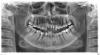

Iren49 Опубликовано 12 июля, 2009 Поделиться Опубликовано 12 июля, 2009 Здравствуйте. В 2000 году мне поставили пластмассовые коронки на передние зубы. в 2006 году. когда я захотела менять их на металлокерамику, то после дентального снимка обнаружили небольшую кисту. Мне надо было уезжать и я не рискнула удалять , тем более времени было 2 недели. В последующие годы я приезжала на небольшой срок в Россию. В этом году я сломала один из этих зубов и решила поменять на металлокерамику. До этого времени мне не направляли на панорамный снимок . Увидев его, я ужаснулась. Не бросайтесь в меня помидорами и не ругайте меня. Я сама себя ругаю за нерасторопливость, но надо что-то делать. На приёме у бюджетного хирурга я испугалась попадать под его скальпель, потому как он не внушил мне доверия, сказав , что не может сказать о результате операции , не был уверен об исходе операции и постоянно консультировался у других. И не знал , снимать пластм. зубы до операции или после. Я решила записаться на консультацию к профессору. и я думаю , здесь , уважаемые доктора , мне подскажут советом. Спасибо. Вот мой снимок Ссылка на комментарий

Зубодер Опубликовано 12 июля, 2009 Поделиться Опубликовано 12 июля, 2009 Здравствуйте. В 2000 году мне поставили пластмассовые коронки на передние зубы. в 2006 году. когда я захотела менять их на металлокерамику, то после дентального снимка обнаружили небольшую кисту. Мне надо было уезжать и я не рискнула удалять , тем более времени было 2 недели. В последующие годы я приезжала на небольшой срок в Россию. В этом году я сломала один из этих зубов и решила поменять на металлокерамику. До этого времени мне не направляли на панорамный снимок . Увидев его, я ужаснулась. Не бросайтесь в меня помидорами и не ругайте меня. Я сама себя ругаю за нерасторопливость, но надо что-то делать. На приёме у бюджетного хирурга я испугалась попадать под его скальпель, потому как он не внушил мне доверия, сказав , что не может сказать о результате операции , не был уверен об исходе операции и постоянно консультировался у других. И не знал , снимать пластм. зубы до операции или после. Я решила записаться на консультацию к профессору. и я думаю , здесь , уважаемые доктора , мне подскажут советом. Спасибо. Вот мой снимок не стану ручаться,потому как не очень хорошо видны зубы в проекции корней которых располагается киста,но...прежде всего надо сделать дентальные Rg чтобы лучше разглядеть каналы этих зубов.кажется там имеется проблема,которую и надо устранить.а после этого с учётом того что Вы постоянно в разьездах и удалить кисту. Ссылка на комментарий

Iren49 Опубликовано 13 июля, 2009 Автор Поделиться Опубликовано 13 июля, 2009 Думаю, что эндодонтическое лечение 23 и 24 зубов, контроль лечения 21 и 22 с последующей резекцией верхушек зубов, которые входят в кисту, цистэктомия (желательно, с костной пластикой) - вот примерный план хирургического лечения. Спасибо за ответ. сегодня я была на приёме у доктора, он направил меня на предоперационные анализы и я поняла, что в среду будут удалять кисту. А про лечение ничего не было сказано. Верно ли это? Ссылка на комментарий

Зубодер Опубликовано 13 июля, 2009 Поделиться Опубликовано 13 июля, 2009 (изменено) Спасибо за ответ. сегодня я была на приёме у доктора, он направил меня на предоперационные анализы и я поняла, что в среду будут удалять кисту. А про лечение ничего не было сказано. Верно ли это?ешё раз повторяю,по этому снимку трудно судить о состоянии каналов,если выложите внутриротовые можно будет говорить определённее.но раз развилась киста то есть шанс что повинны леченные зубы. Изменено 13 июля, 2009 пользователем Зубодер Ссылка на комментарий